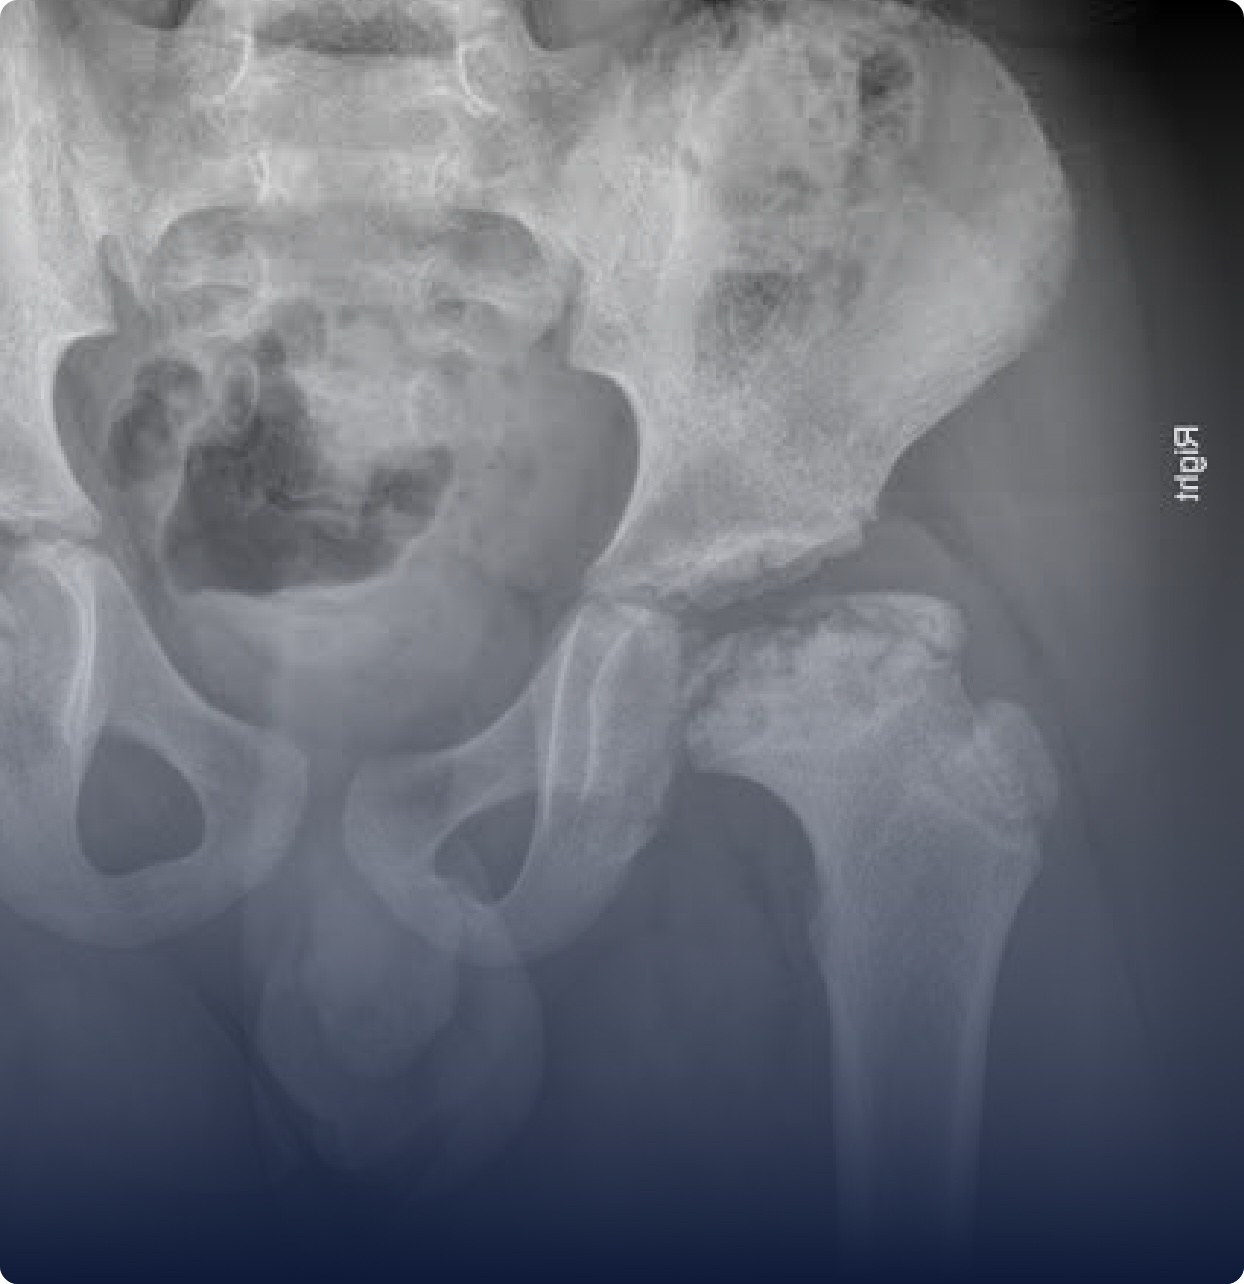

Displasia do quadril

É uma alteração no encaixe do quadril presente desde o nascimento. Quando não diagnosticada cedo, pode comprometer a marcha da criança e causar dores na vida adulta.

Doença de Perthes

É uma condição em que há interrupção temporária da circulação sanguínea na cabeça do fêmur, o que leva à necrose óssea. Isso pode causar dor, mancar e limitar os movimentos do quadril da criança.

Displasia do quadril: a importância do diagnóstico precoce

Desde o momento em que os pais recebem a notícia de que seu bebê pode ter uma condição no quadril, é natural que surjam dúvidas, preocupações e até certo receio.